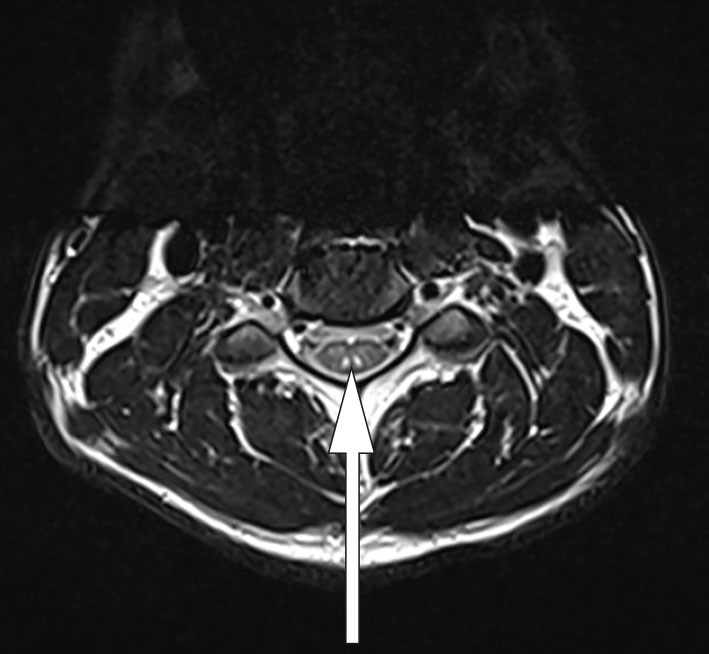

On contrast-enhanced MRI of the central nervous system on day 5, a sagittal section of a T2-weighted image showed a subtle high signal intensity in the spinal cord at C2/C3 (Figure 1), and an axial section showed contrast accumulation at the dorsal column (Figure 2). However, there was no uptake of contrast along lumbar nerve roots or the conus medullaris.

The findings indicated nerve injury in both the spinal cord and lower limbs. With a non-elevated protein level in the cerebrospinal fluid and no contrast accumulation in the lumbar area on MRI, the findings were not consistent with Guillain-Barré syndrome. MRI of the spinal cord (Figure 2) revealed a so-called inverted V or 'rabbit ears' sign. This is referred to as subacute combined degeneration and is characteristic of demyelination of the dorsal column caused by vitamin B12 deficiency (5).